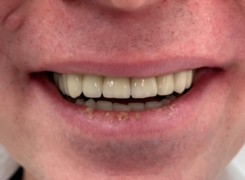

Pan Ryszard trafił do Naszego Gabinetu z jasno sprecyzowanym oczekiwaniem. Miał 84 lata i chciał odzyskać możliwość swobodnego spożywania posiłków oraz poprawienia sobie komfortu życia a także prosił aby przywrócić mu piękny uśmiech jakim cieszył się przed laty. Już na początku pierwszej rozmowy zastrzegł, że interesuje go wyłączenie rozwiązanie uzupełnieniem protetycznym stałym. Nie miał zamiaru użytkować żadnych protez ruchomych. Mając na uwadze powyższe wykonaliśmy Panu Ryszardowi zdjęcie pantomograficzne oraz badanie tomograficzne szczęki i żuchwy na postawie których zapanowywaliśmy Pacjentowi optymalne rozwiązanie – stałe uzupełnienie protetyczne w postaci 28 koron cyrkonowych zamontowanych do dwóch belek cyrkonowych które będą przymocowane do 16 implantów w konfiguracji 8 wszczepów w szczęcie 8 w żuchwie. Po omówieniu powyższego planu przystąpiliśmy do Wspólnej pracy której efekty w poszczególnych etapach prezentujemy poniżej.